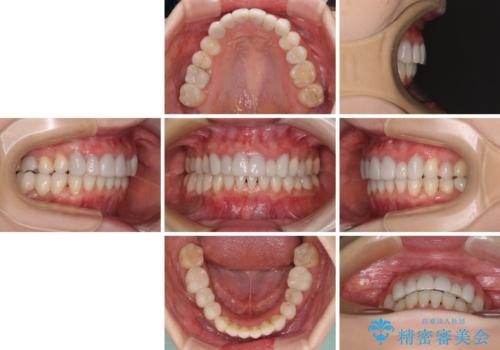

前歯のデコボコと奥歯の咬み合わせをインビザラインで改善

- 上下前歯のデコボコと奥歯の欠損を気にして来院された患者様です。

右下の欠損分は奥歯が倒れ込んでスペースがなくなっていたため、矯正治療により本来の位置に歯を移動させ、オールセラミックブリッジによる欠損補綴治療を行うこととしました。

全顎的にセラミッククラウンが多く装着されているため、インビザラインによる矯正治療を行うこととしました。

右下は移動量が多いため、十分な移動が達成されない場合はワイヤー装置を使用する予定としておりましたが、しっかりとマウスピースを装着してくださったため、前歯とともに十分に歯を動かすことができました。